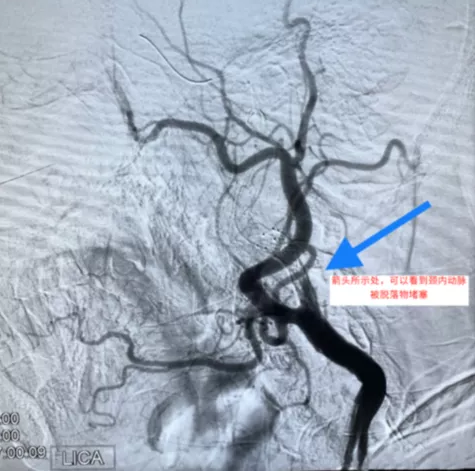

就在手术在有条不紊的进行时,因为李大爷栓子量太大,以至于放完支架后,栓子完全堵塞了脑保护伞,造成颈内动脉闭塞,如果不及时开通,可能会有生命危险。这个时候绝对需要术者沉着应对。刘加春主任凭借多年临床经验,用特殊方法把脑保护伞小心回收,收完后,李大爷的血管恢复正常。术后,在脑保护伞内见到大量的脱落斑块(图)。